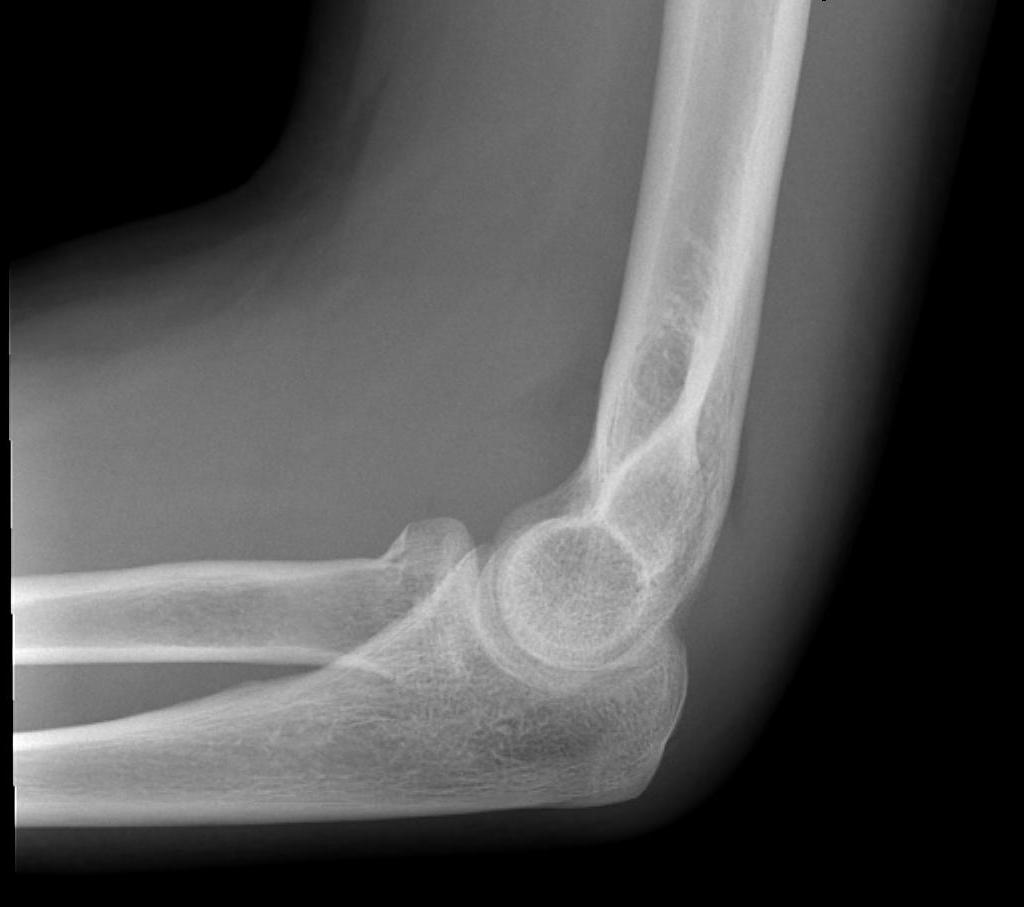

Bag of bones / nonoperative management

Initial injury in elderly patient

Elbow post treatment in cast

Indication

Patient elderly and not operative candidate

Technique

Initial rest in plaster then mobilisation

Results

- 40 "elderly and low demand" patients treated non-op

- 5 year mortality 40%

- 50% non union

- DASH score 38/100

- modest function, but avoids risks